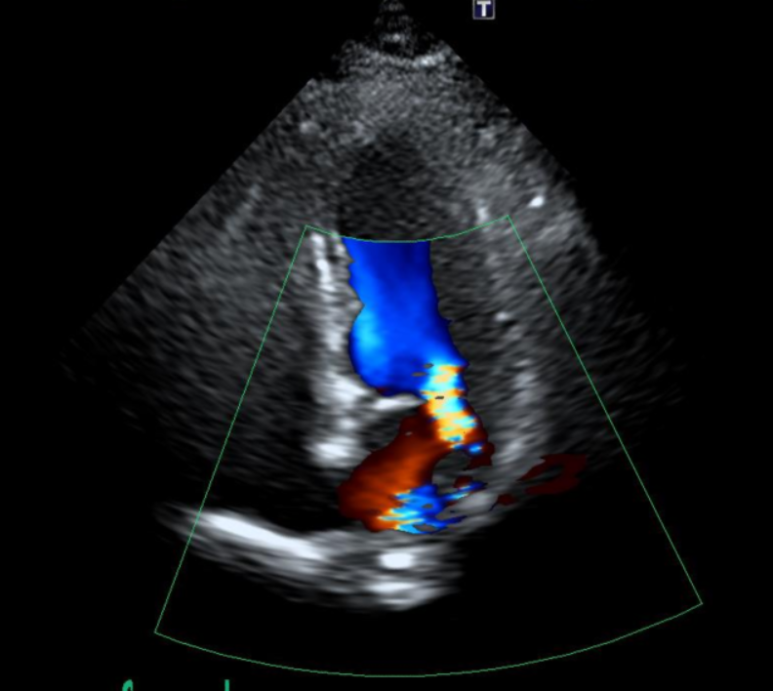

심장판막질환